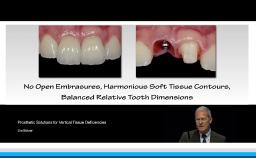

This lecture presents a concept for choosing the type of reconstruction and material for highly esthetic outcomes. Due to the number of restorative possibilities, the selection of an ‘ideal’ material is getting more and more complex. Advantages of all-ceramic materials over traditional metal-ceramics include their tooth-like color and their enamel-like translucency. The main limitation of ceramics is their brittleness, leading to a risk for fracture during clinical service. This lecture discusses the development of modern ceramics with increased stability to reduce this risk, with a focus on high-strength ceramic zirconia and its potential as an alternative to metal. For the processing of zirconia, numerous computer-aided manufacturing procedures are available today. Moreover, multiple clinical studies show promising results for zirconia-based tooth and implant reconstructions.